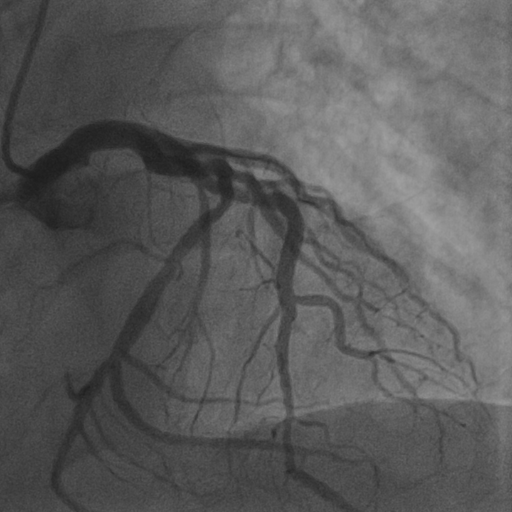

4.1 XACV Dataset

We collect 111 complete records of coronary artery X-ray videos from 59 patients, encompassing the injection, flow through the blood vessels around the heart, and dissipation of the contrast agent. Subsequently, we establish the XACV (X-ray Angiography Coronary Video) dataset. Each video consists of an average of 86 frames of high-resolution coronary artery X-ray images, with an equal distribution of left and right coronary arteries. We invite experienced radiologists to annotate the vascular regions, focusing on one or two frames where the contrast agent is most prominent in each video. These annotations are used only for evaluation in our method, not for training, maintaining the unsupervised nature of our approach. The data collection protocol involves several key steps, including patient preparation with informed consent and metal object removal, image capture using a Philips Allura Xper FD20 machine for standardized frontal (PA) and lateral views, DICOM file storage, and de-identification for patient privacy. Experienced radiologists perform diagnostic annotations using standardized tools and methods, with multiple annotations to enhance accuracy. Quality control measures, secure data management, and strict adherence to ethical guidelines and privacy regulations are implemented throughout the process. The XCAD dataset contains only a single image, and the CADICA video dataset does not provide corresponding ground truth. Therefore, in the following experiments, we conduct all the analyses on our collected XACV dataset and the corresponding GT for each sequence. In Figure 5, we show that compared to other publicly available datasets, XCAD (Ma et al., 2021) and CADICA (Jiménez-Partinen et al., 2024), our dataset exhibits finer annotations in the vascular regions, providing an advantage for future related tasks. The development and use of our dataset have been approved by our institution’s IRB. We will make the XACV dataset publicly available.